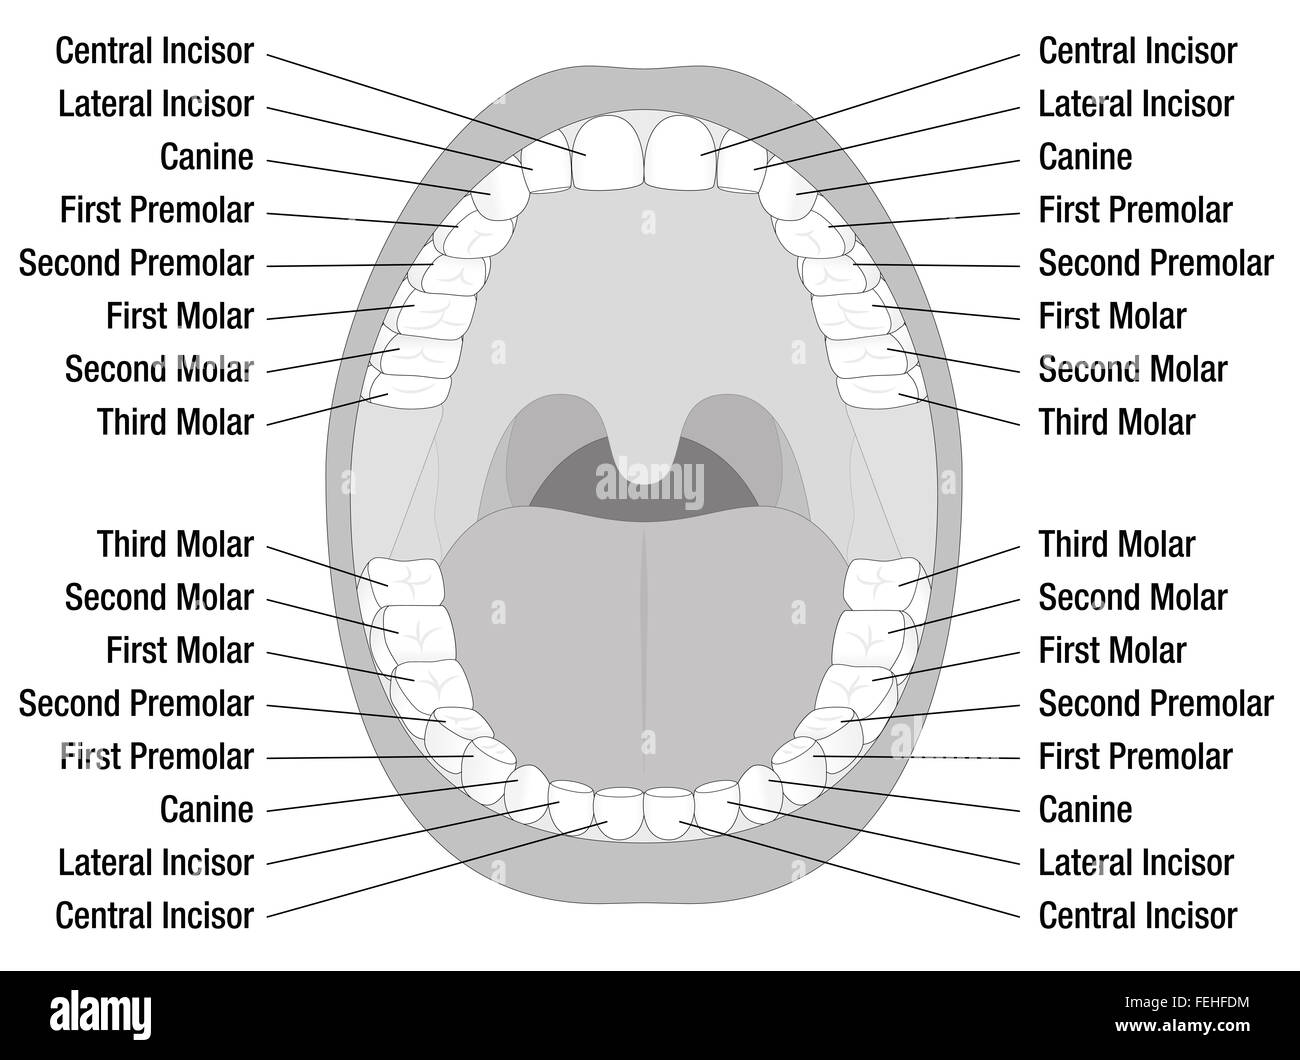

- Ouvrir la bouche dents adultes modèle avec des mâchoires supérieure et inférieure et de ses trente-six dents permanentes. Banque D'Imageshttps://www.alamyimages.fr/image-license-details/?v=1https://www.alamyimages.fr/photo-image-ouvrir-la-bouche-dents-adultes-modele-avec-des-machoires-superieure-et-inferieure-et-de-ses-trente-six-dents-permanentes-84712216.html

- Ouvrir la bouche dents adultes modèle avec des mâchoires supérieure et inférieure et de ses trente-six dents permanentes. Banque D'Imageshttps://www.alamyimages.fr/image-license-details/?v=1https://www.alamyimages.fr/photo-image-ouvrir-la-bouche-dents-adultes-modele-avec-des-machoires-superieure-et-inferieure-et-de-ses-trente-six-dents-permanentes-84712216.htmlRFEWPY88–- Ouvrir la bouche dents adultes modèle avec des mâchoires supérieure et inférieure et de ses trente-six dents permanentes.

Surface à mâcher dents humaines mâchoire inférieure supérieure, clinique dentaire dentaire Illustration de Vecteurhttps://www.alamyimages.fr/image-license-details/?v=1https://www.alamyimages.fr/surface-a-macher-dents-humaines-machoire-inferieure-superieure-clinique-dentaire-dentaire-image565453538.html

Surface à mâcher dents humaines mâchoire inférieure supérieure, clinique dentaire dentaire Illustration de Vecteurhttps://www.alamyimages.fr/image-license-details/?v=1https://www.alamyimages.fr/surface-a-macher-dents-humaines-machoire-inferieure-superieure-clinique-dentaire-dentaire-image565453538.htmlRF2RRXHN6–Surface à mâcher dents humaines mâchoire inférieure supérieure, clinique dentaire dentaire

La mâchoire inférieure est déposée. Dans la partie inférieure de la figure se trouve le palais dur formant le toit de la bouche et entouré par la partie supérieure des dents, v Illustration de Vecteurhttps://www.alamyimages.fr/image-license-details/?v=1https://www.alamyimages.fr/la-machoire-inferieure-est-deposee-dans-la-partie-inferieure-de-la-figure-se-trouve-le-palais-dur-formant-le-toit-de-la-bouche-et-entoure-par-la-partie-superieure-des-dents-v-image367210369.html

La mâchoire inférieure est déposée. Dans la partie inférieure de la figure se trouve le palais dur formant le toit de la bouche et entouré par la partie supérieure des dents, v Illustration de Vecteurhttps://www.alamyimages.fr/image-license-details/?v=1https://www.alamyimages.fr/la-machoire-inferieure-est-deposee-dans-la-partie-inferieure-de-la-figure-se-trouve-le-palais-dur-formant-le-toit-de-la-bouche-et-entoure-par-la-partie-superieure-des-dents-v-image367210369.htmlRF2C9BTG1–La mâchoire inférieure est déposée. Dans la partie inférieure de la figure se trouve le palais dur formant le toit de la bouche et entouré par la partie supérieure des dents, v

Les noms des dents des dents permanentes. Illustration sur fond blanc. Banque D'Imageshttps://www.alamyimages.fr/image-license-details/?v=1https://www.alamyimages.fr/photo-image-les-noms-des-dents-des-dents-permanentes-illustration-sur-fond-blanc-95042352.html

Les noms des dents des dents permanentes. Illustration sur fond blanc. Banque D'Imageshttps://www.alamyimages.fr/image-license-details/?v=1https://www.alamyimages.fr/photo-image-les-noms-des-dents-des-dents-permanentes-illustration-sur-fond-blanc-95042352.htmlRFFEHFDM–Les noms des dents des dents permanentes. Illustration sur fond blanc.